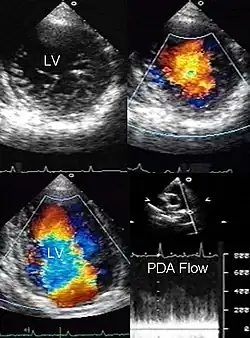

El colapso circulatorio cardíaco afecta a los vasos del corazón, tales como la aorta y es casi siempre fatal. Se denomina en ocasiones insuficiencia circulatoria «aguda».

Las principales causas de una insuficiencia circulatoria son una función cardíaca comprometida, trastornos a nivel de los vasos sanguíneos y un volumen circulante disminuido o hipovolemia. La bomba cardíaca puede presentar trastornos en la frecuencia cardíaca, en la contractilidad del músculo cardíaco o por defectos en el volumen de precarga o poscarga en oposición al vacío del ventrículo izquierdo. La vasoconstricción, vasodilatación o vasoplejía son algunos de los trastornos de los vasos sanguíneos que pueden comprometer la circulación sanguínea.

El tratamiento debe ocurrir sin prórroga, dependiendo de la causa. En patologías de la bomba cardíaca que demuestre una fracción de eyección de la sangre menor al 50 % o una fracción de acortamiento del músculo cardíaco mayor del 35 % se suele administrar un medicamento inotrópico o digitálicos. Si hay alteraciones de ritmo cardíaco se sigue un tratamiento médico. Por lo general se emplea la atropina, adrenalina o dobutamina para disminuciones de la frecuencia cardíaca y digitálicos, amiodarona o adenosina más cardioversión en la frecuencia cardíaca elevada. Para trastornos de la conducción eléctrica del corazón como bloqueos, puede ser necesaria la colocación de marcapasos. Para mejorar la precarga se debe restituir el volumen circulante y en la poscarga se corrige el trastorno de base, como una coartación o estenosis aórtica, una aneurisma o la hipertensión arterial.